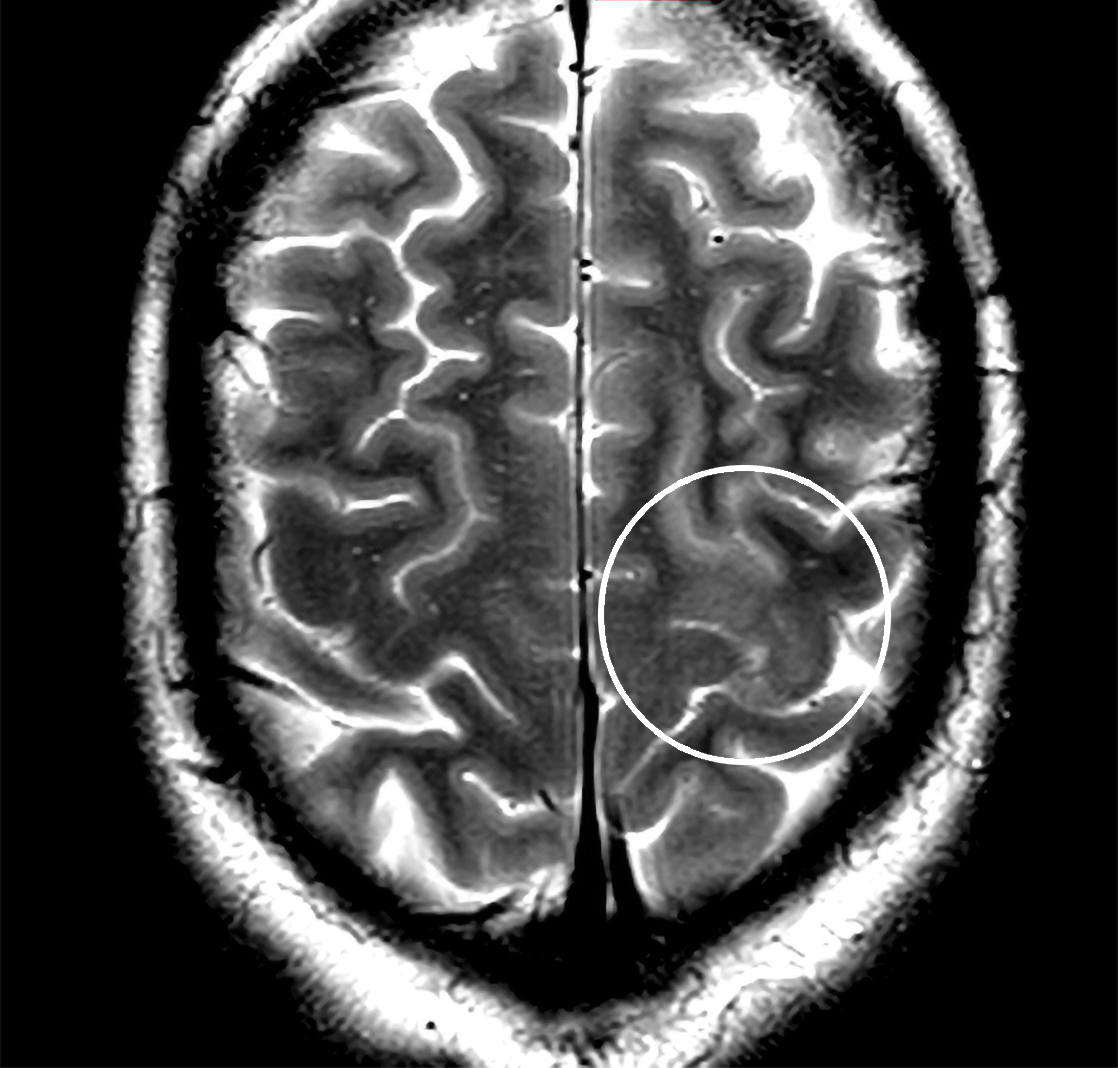

En mann i slutten av 40-årene ble innlagt med akutt innsettende slagsymptomer. Utredningen avslørte en sykdom som ofte glemmes, men som forekommer i økende grad og er behandlingstrengende. Les mer her .